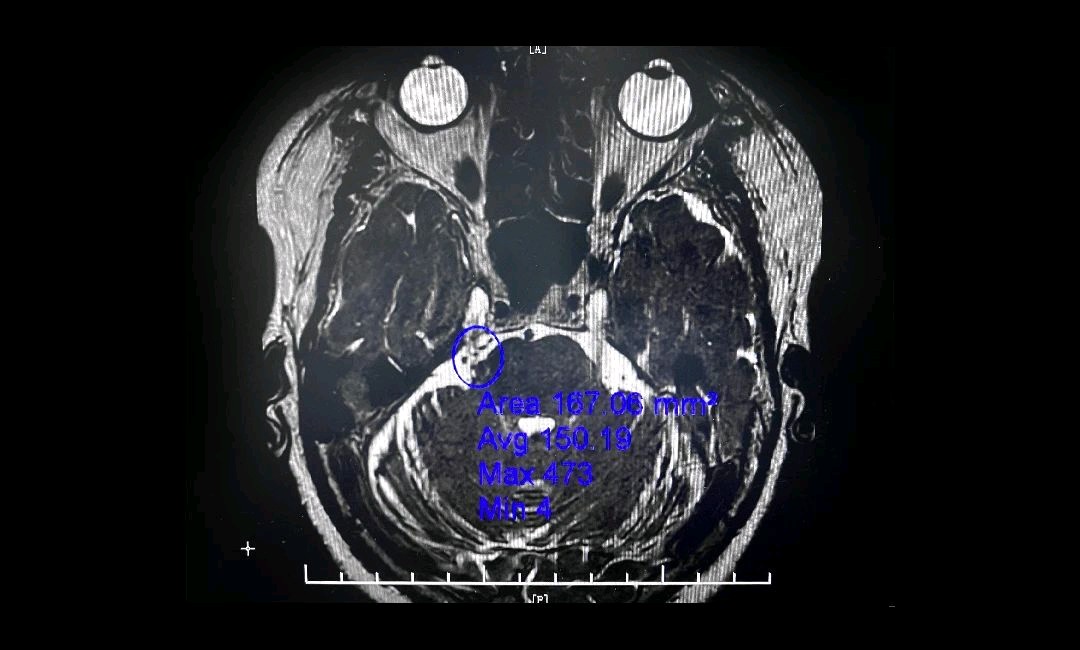

《河南商报》2023年6月27日报道,56岁的姜女士患三叉神经痛已有三年多了,平时靠吃药控制病情,然而最近由于天气太热,姜女士连续吹了几天空调后,三叉神经痛又犯了!这次虽然增加剂量服用药物,但疼痛仍不能缓解,疼得她每天刷不了牙、吃不下饭、说不出话,到医院检查后发现姜女士的三叉神经痛是颅内血管压迫三叉神经所致,这次发作可能是吹冷气诱发的。

微血管减压术是现代神经外科典型的微创手术之一,仅通过患者耳后发际内4-5cm的切口,于显微镜下探查三叉神经走行区,将所有可能产生压迫的血管、蛛网膜条索都“松解”开,并将这些血管以Tefflon垫片与神经根隔离。一旦责任血管被隔离,产生刺激的根源就消失了,三叉神经核的高兴奋性就会随之消失,恢复正常。绝大多数患者术后疼痛立即消失,并保留正常的面部感觉和功能,不影响生活质量。